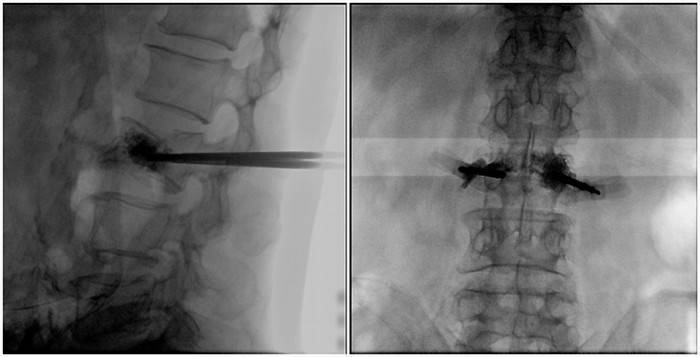

(2)術中切口5毫米,借助大視野平板C臂機PLX119C的高清圖像,確定進針的方向及進針的深度。經椎弓根向椎體置管,建立通道,插入骨擴張器(球囊)。球囊擴張恢復椎體高度,并在椎體內形成空腔,確定骨水泥的注入劑量,并注入骨水泥觀察其擴散情況。

(3)注射過程需要C臂透視來查看骨水泥的分布情況,預防骨水泥外露進入椎管內引起神經損傷。椎骨體內骨水泥填充完好以后,拔出工作套筒按壓止血,并繼續俯臥位十分鐘,等待骨水泥硬化,最終手術圓滿完成。